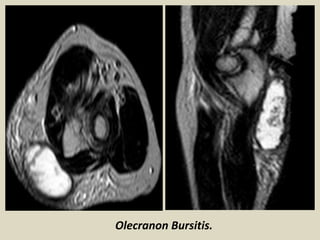

The olecranon bursa is a subcutaneous bursa that provides almost frictionless motion

between the skin, the subcutaneous tissues and the olecranon. Because of its superficial

location, it is a common site for injury, inflammation and infection. Repeated work-

related trauma results in bursitis as seen in “student's elbow” or “miner's elbow.

Olecranon bursitis is identified by clinical diagnosis, and imaging is rarely performed in

this context. In patients with advanced infection, MRI is sometimes requested to evaluate

abscesses or osteomyelitis. Incidental diagnosis of olecranon bursitis on ultrasound and

MRI is frequent from concomitant inflammation and effusion in the olecranon bursa

secondary to trauma, rheumatoid arthritis and other inflammatory diseases.

Magnetic resonance T2 fat sat image with fluid in the olecranon bursa.

Olecranon Bursitis.